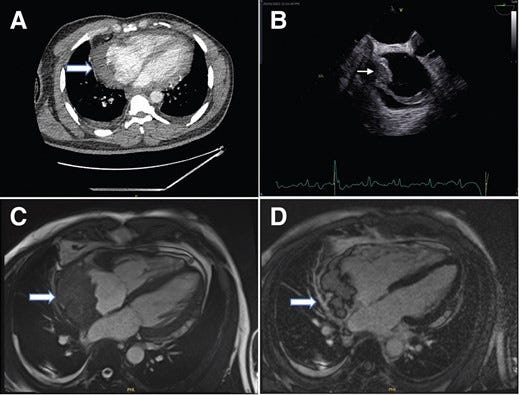

(A) Contrast computed tomography thorax (using Omnipaque 350 contrast agent) showing a filling defect in the right atrium’s lateral wall. (B) This was also seen in the transoesophageal echo as seen in the image on the right. (C) Four-chamber balanced SFPP Cine sequence revealed a large mass (6 × 3 cm) with irregular margins which appears to originate from the pericardium and compressing the right atrium. (D) Four-chamber delayed gadolinium enhancement sequence showed heterogeneous enhancement of the mass and no myocardial late gadolinium enhancement.

In Case 1, a 49-year-old Black African male presented with chest pain and breathlessness after a COVID-19 vaccine. Initially treated for pericarditis, he returned with worsening symptoms. Echocardiography revealed pericardial effusion and cardiac tamponade. Imaging confirmed a right atrial mass diagnosed as malignant biphasic mesothelioma. He died 4 months after diagnosis. In Case 2, a 43-year-old Caucasian male developed breathlessness and fever post-COVID-19 vaccine. Imaging identified a large posterior pericardial mass, later diagnosed as synovial sarcoma. Chemotherapy yielded minor tumour reduction, but he succumbed to his illness, spending his final days in a hospice.